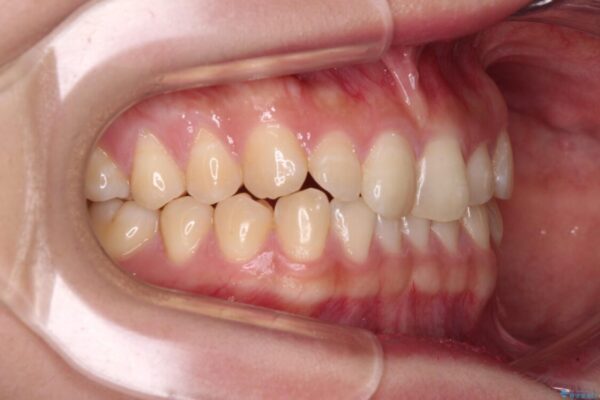

治療前

• 治療途中の奥歯と矯正治療の後戻り インビザライン・ライトによる矯正治療 治療前画像

根管治療を行ったままの奥歯と、矯正治療の後戻りを気にして来院された患者様です。

治療計画

根管治療された歯に症状はなく、オールセラミッククラウンにて補綴治療を行うこととしました。

矯正治療の後戻りは軽微であったため、インビザラインの簡易パッケージであるインビザライン・ライトを用いて歯列を整えることとしました。